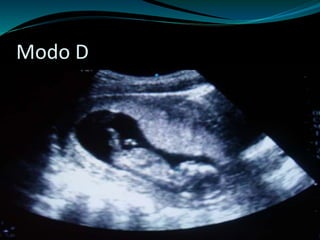

 Modo D

Modo D

Tipos de Ultra-Sonografia  Modo A  Modo M  Modo B  Modo D